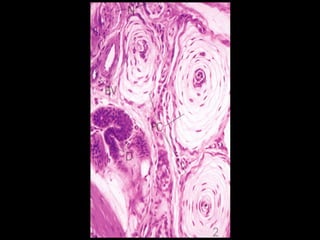

Pacinian corpuscles

 Encapsulated receptors

 Ovoid structure resembling

a hemisected onion

 Nerve ending is

surrounded

by concentric lamellae of

flattened cells

 Found in hypodermis and

deed fascia tissues

 Respond to vibrations and

deep pressure